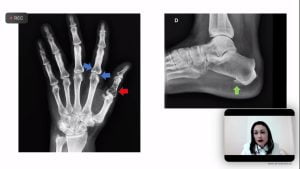

Discussão de casos clínicos: Artrite Psoriásica e iJAK

No dia no 31 de agosto a Sociedade de Reumatologia de Brasília realizou a 3ª Reunião Científica – discussão de casos clínicos. No encontro virtual moderadora Penélope Palominos falou sobre o tema: Artrite Psoriásica e iJAK.